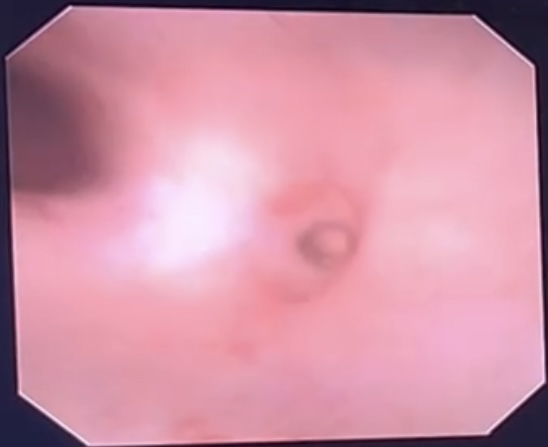

在与院内多位专家沟通和探讨后,周主任决定采用输尿管软镜联合负压吸引鞘激光碎石。该方法在减少肾脏内压力的同时,还可以提高清石率。术中顺导丝放入可弯曲输尿管引导鞘至输尿管肾盂交界处,鞘内置入输尿管软镜,按序检查肾盂及上中下盏,右肾上盏内见多枚结石。此外,在下盏附近发现一个细小的开口,其内可隐约看到结石,这就是肾盏憩室内的那一颗结石。用200um钬激光光纤将上盏的结石击碎后,周主任巧妙地控制输尿管软镜进入憩室内,用激光将剩余结石击碎,并利用负压将所有结石残渣吸出,手术非常顺利。